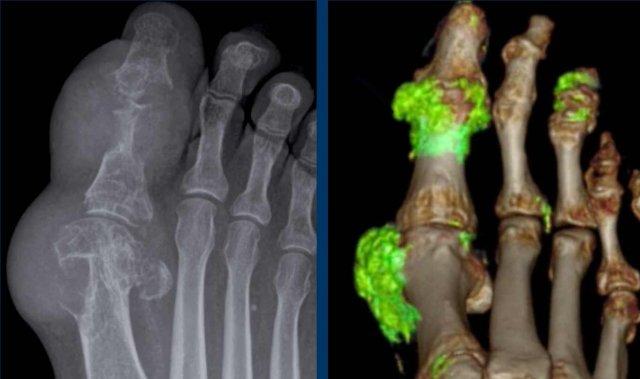

Biến dạng bút chì trong cốc

A. Biến dạng bút chì trong cốc tại ngón chân thứ 1 và thứ 5.

B. Tiêu xương đầu ngón (acro-osteolysis) với tiêu xương chỏm đốt ngón xa của ngón 2-4 và 5.

Có bào mòn xương tại khớp bàn ngón chân (MTP) 2 và 3.

Viêm màng xương trong viêm khớp vảy nến

Đây là bệnh nhân viêm khớp vảy nến.

Lưu ý hình ảnh viêm màng xương mờ nhạt tại đốt ngón xa của ngón 1 bên phải (đầu mũi tên).

Có các bào mòn xương nhỏ tại chỏm đốt ngón xa của ngón 2 và 3 bên trái (mũi tên trắng).